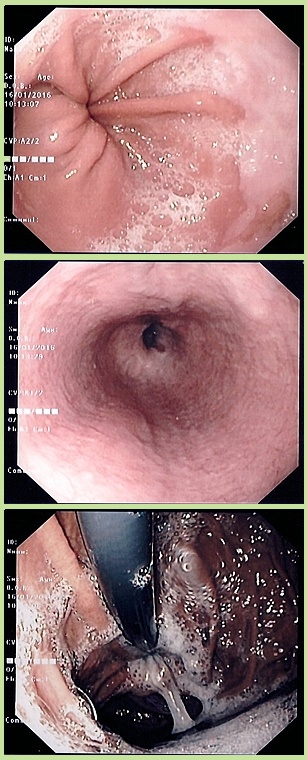

In questa prima si vede il mio esofago con quella roba chiusa che sarebbe il cardias. La foto è ripresa dall’alto verso il basso. Oltre quella specie di buco c’è il mio stomaco.

Questo invece credo che sia il duodeno con in fondo il piloro. La foto è presa da sinistra verso destra quasi in orizzontale (guardando la propria pancia)

Per ultima la più disgustosa. Se non ricordo male la descrizione del medico, la foto è presa dal basso verso l’alto e mostra lo stomaco. Il tubo nero in alto è il tubo endoscopico che sbuca dal cardias, scende verso il basso e poi fa una curva di 180 facendo praticamente un selfie. Quella parte più scura è il fondo dello stomaco, che in realtà si chiama così ma è la parte superiore. Questa si gonfia di aria e preme sull’esofago causando le mie disfagie. Si vede bene una specie di stallatite di muco biancastro sulla cui natura ho già parlato diffusamente.